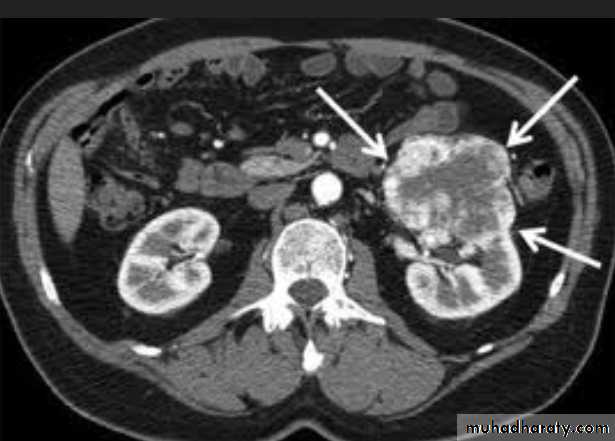

A 55-year-old man with hematuria , What's this study and abnormal finding ?

Ct enhanced

Renal cyst type 4 with calcification and peripheral enhancement needs radical nephrectomyBosniak's class II renal cysts. A, CT scan shows right renal cyst with thin internal septation.